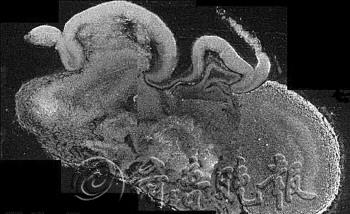

| 显微镜下“迷你人脑”的透视图片。 据每日邮报 |  | 科学家对同样大小的普通胚胎内正在发育的大脑(左图)和实验室培育出的“迷你人脑”(右图)进行的比较。 据每日邮报 |

始于人体干细胞 “迷你人脑”培养始于人体干细胞,由奥地利分子生物技术研究所与英国、德国等方面的研究人员合作完成。 研究人员利用特别搭配的多种营养物质,以此培养出可以形成脑和神经系统的神经外胚层。神经外胚层组织碎片被放置在一个旋转生物反应器内,在有氧气循环和养分供给的环境下逐渐形成“类脑器官”。 开始培养一个月后,神经外胚层碎片组成视网膜、大脑皮层等大脑组成部分。两个月后,“迷你人脑”长成,尽管直径仅4毫米,只有豌豆大小,结构细密程度难以与发育完成的人脑相比,却拥有能够放电的神经元和多种脑神经组织。 “迷你人脑”问世标志着科学家首次成功以“三维”形式复制人脑组织形成过程。